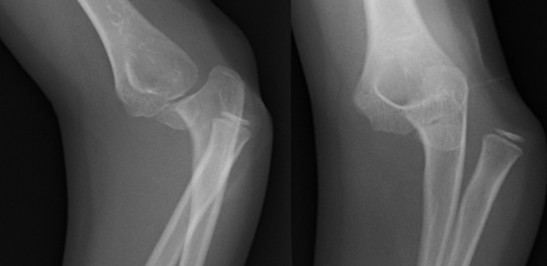

Ellenbogenluxation bei 7-jährigem Kind

Ellenbogenluxation mit Sprengung des proximalen radio-ulnaren Gelenkes bei einem 7-jährigen Mädchen.

Ellenbogenluxation mit Sprengung des proximalen radio-ulnaren Gelenkes bei einem 7-jährigen Mädchen.